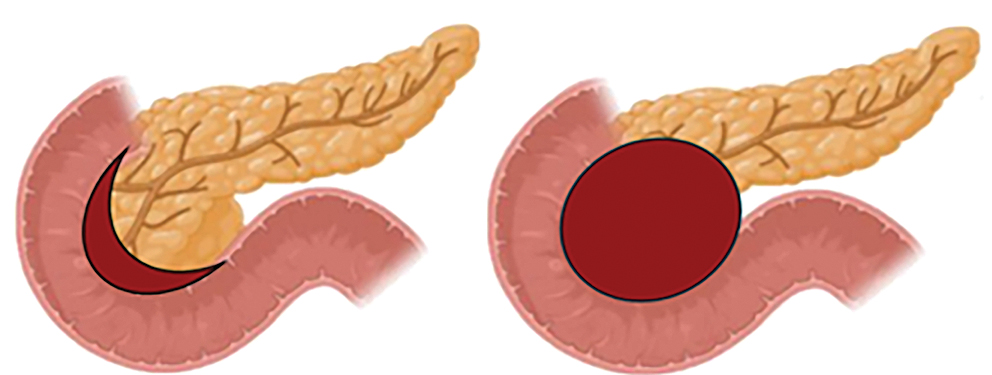

A groove pancreatitis (GP) a krónikus pancreatitis egy ritka, anatómiailag lokalizált formája, amely a pancreasfej, a duodenum és a közös epevezeték közötti területet, az ún. „groove” (vályú) régiót érinti (1. ábra). A kórképet először Becker és Mischke írták le 1973-ban, fibrotikus pszeudotumor formájában ezen anatómiai területen (1). Két fő morfológiai megjelenés különíthető el: a pure („tiszta”) típus, amely során a gyulladás kizárólag a groove régióra korlátozódik, és a szegmentális típus, ahol a gyulladás a pancreasfejet is érinti (2). A krónikus pancreatitis ezen paraduodenalis formája elsősorban a 60 év feletti, alkoholt rendszeresen fogyasztó férfiaknál jelentkezik (3, 4).